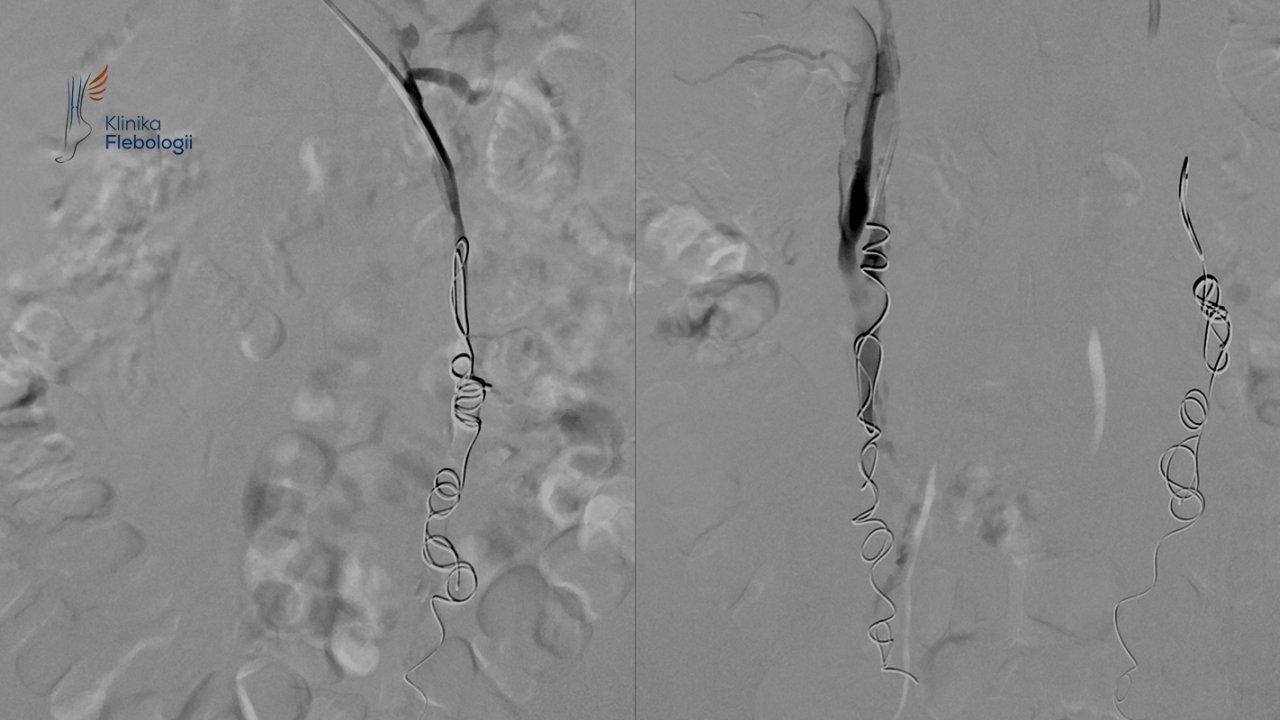

Flebografia i embolizacja żył jajnikowych

Wykorzystujemy ją rutynowo w diagnostyce niewydolności żylnej miednicy, ocenie utrudnienia odpływu na poziomie dużych żył (głównej dolnej i żył biodrowych), czy przy ocenie skomplikowanych malformacji naczyniowych.